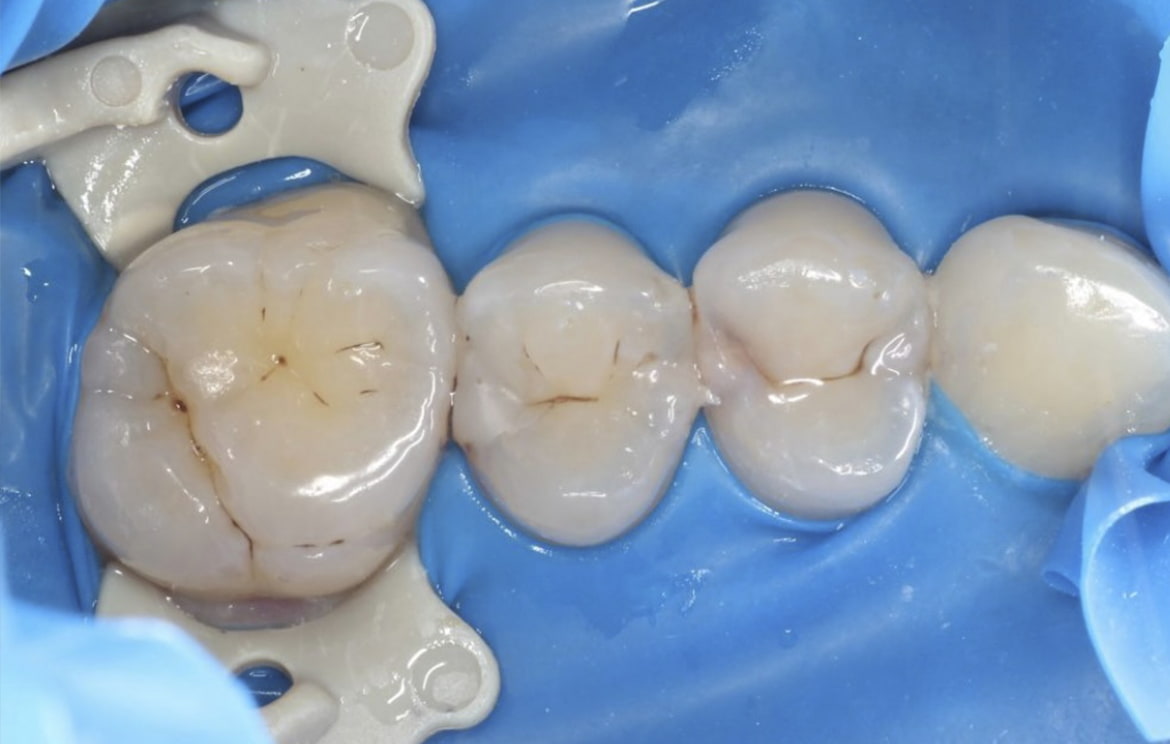

Наши работы